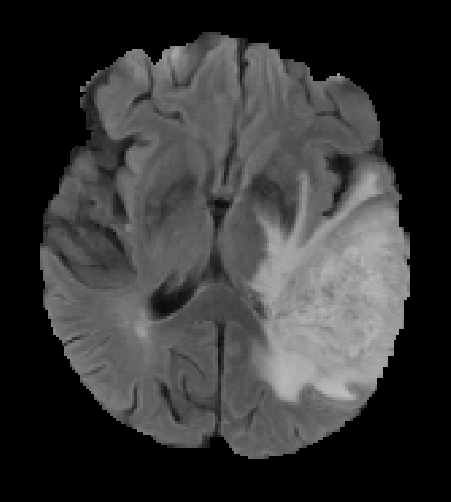

The proposed model outperforms some of the ensemble approaches which is shown in Table 4. Fig. 2 shows the successful segmentation of the tumor. The false positive segmentation voxels are removed in the post-processing. The network fails to segment the tumor for some HGG images and many LGG images. One such segmentation failure is shown in Fig. 3. The failure of the network is observed for: 1) small size of the entire tumor, 2) small size of necrosis, and 3) absence/small size of enhancing tumor. Fig. 4 depicts the box plot of the evaluation metrics, where the red marked cases shows the segmentation failure.

Refer to caption

(a)

(b)

(c)

(d)

Figure 2: Correct segmentation results of the network (a) FLAIR slice (b) Ground truth (c) Segmentation without post-processing (d) Segmentation after post-processing.